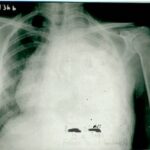

1991 yılında az diferansiye fibröz malign mezotelioma teşhisi konulan 53 yaşındaki kadın hasta, çok düşkün haldeyken immünomodülatör tedavi ile 9 ayda tam iyileşme sağladı. 2000 yılında hasta remisyondaydı ve 9 yıl boyunca hastalık belirtisi göstermedi.

Nefes darlığı, göğüs ağrısı - plevral sıvı

Ödem kayboldu, radyoloji normale yakın

Tetkiklerde sol plevra boşluğunda sıvı saptandı.

Torakoskopi ve Coparvacs uygulamasına rağmen akciğerde tam ekspansiyon sağlanamadı.

Ödem kaybolmuştu, dispne ve taşikardi düzelmişti. İki ay daha aynı tedaviye devam edildi.

Radyolojik bulgular normale yakın hale gelmişti ve immünomodülatör tedaviyi kesmesi önerildi.